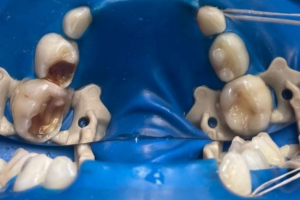

Семейная областная стоматология "Кидди Дентал" - это команда компетентных врачей, каждый из которых знает и любит свое дело. Опыт наших врачей, использование современного оборудования и надежных материалов позволят проводить лечение любой сложности.